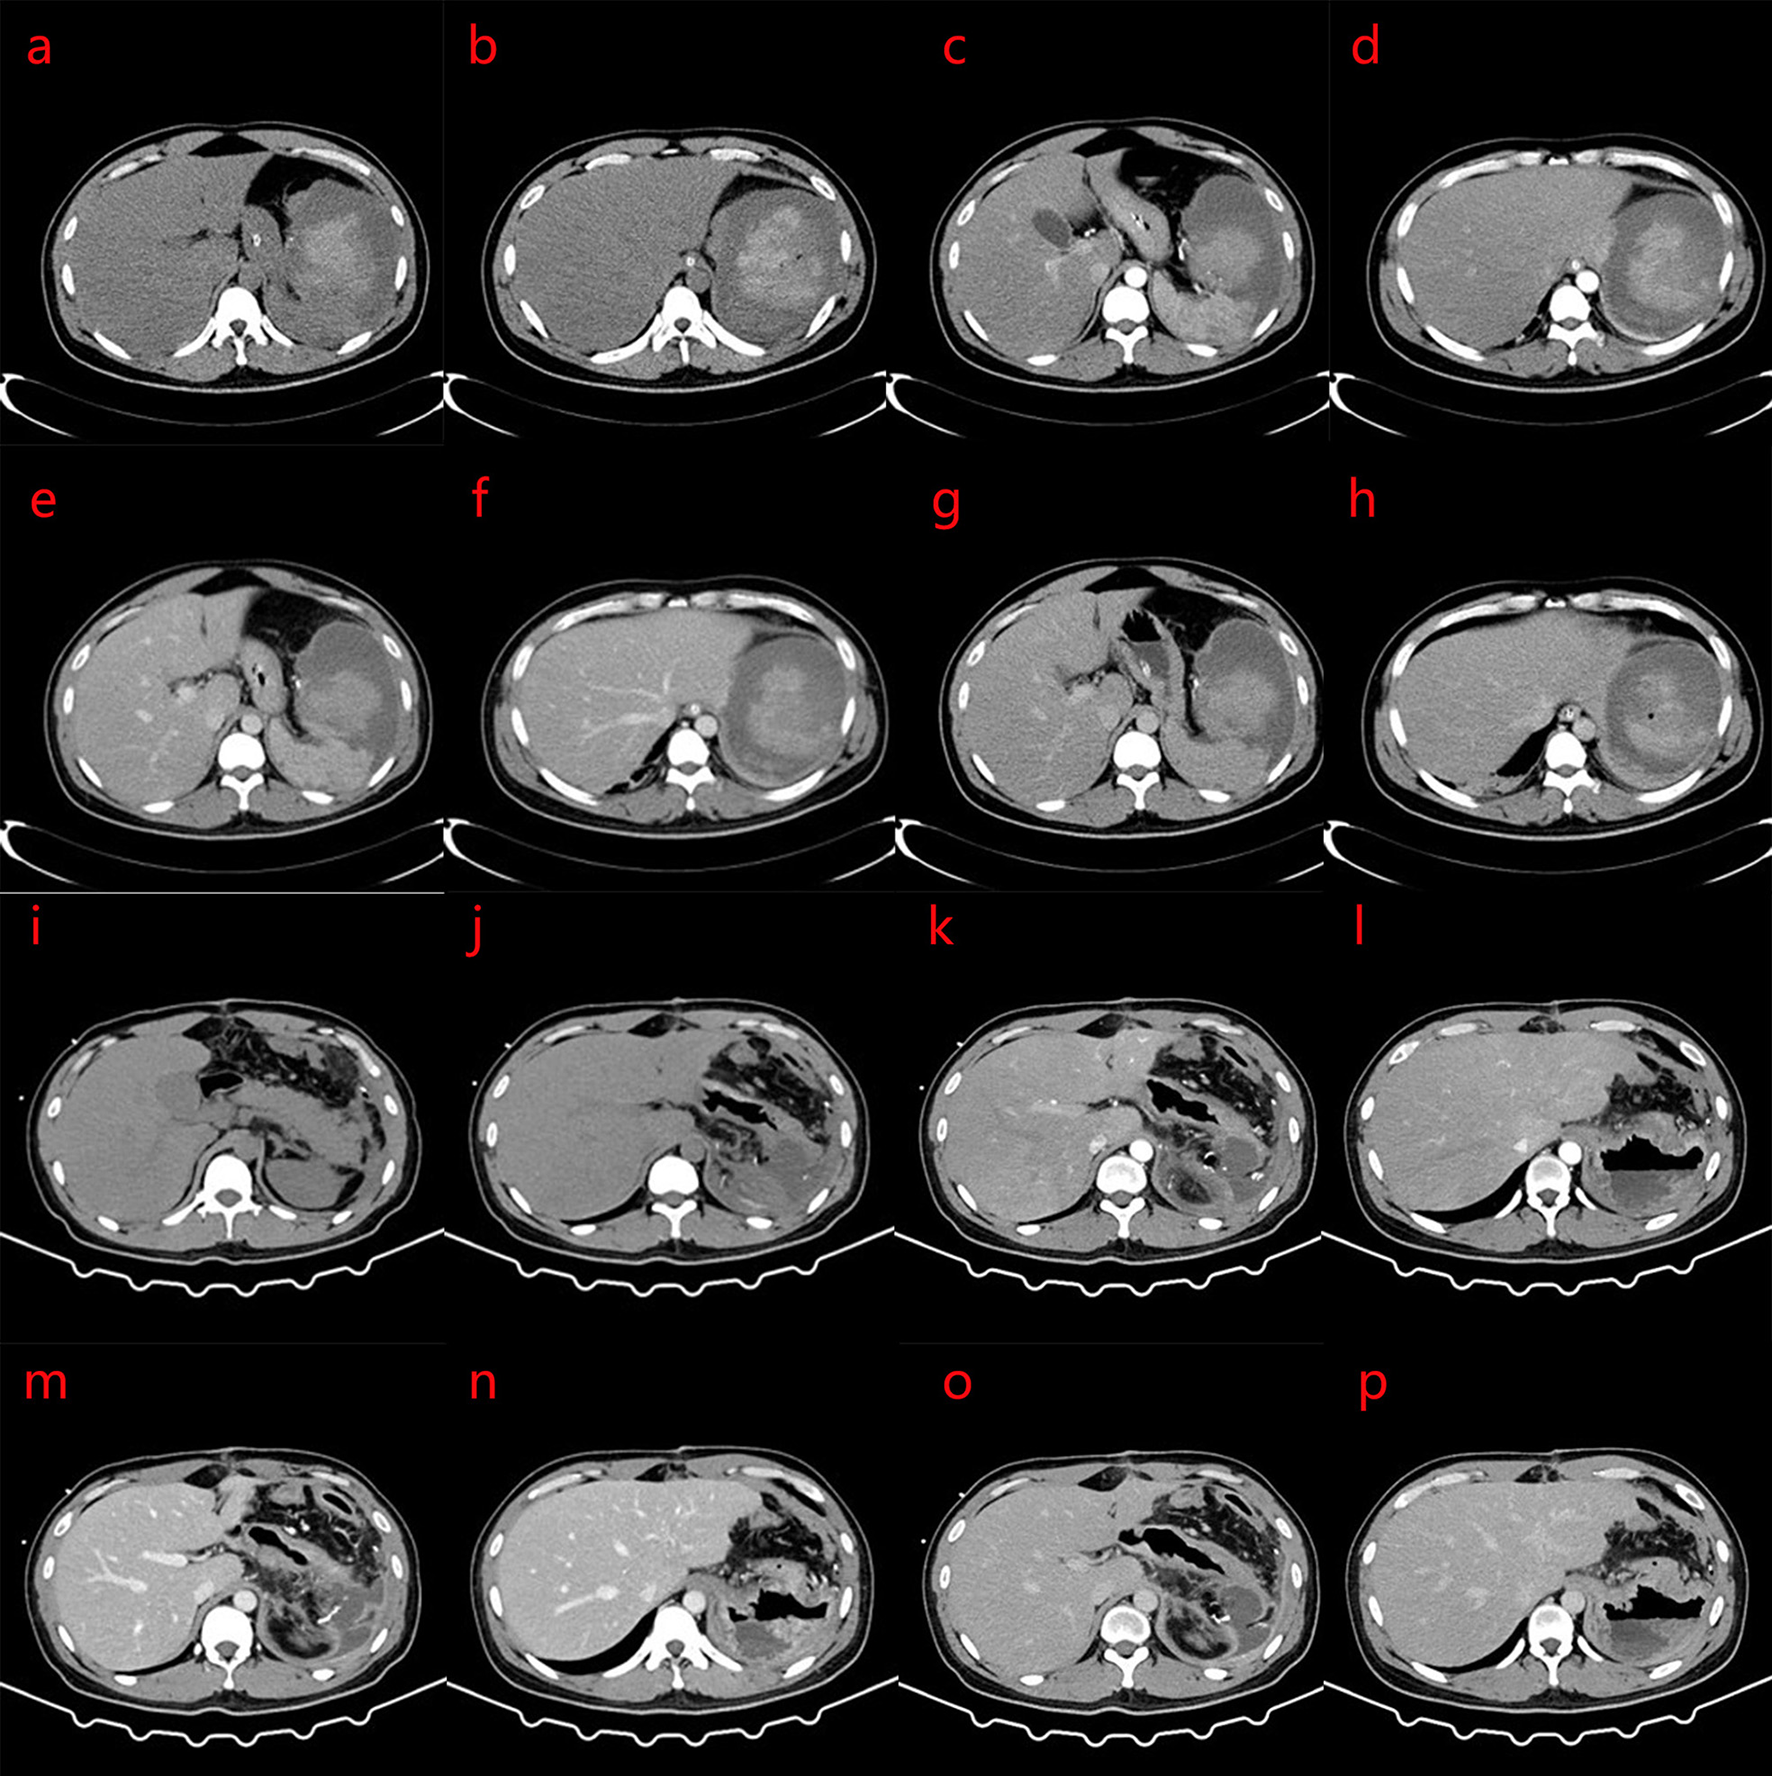

The activated partial thromboplastin time was 11.6 s, fibrinogen was 3.36 g/L, and D-dimer was 9.92 mg/L FEU. Albumin was 36 g/L, potassium was 4.5 mmol/L, sodium was 135 mmol/L, white blood cell count was 13.1 × 109/L (normal 3.5–9.5 × 109/L), hemoglobin levels were 74 g/L, and the platelet count was 716 × 109/L (normal, 125–350 × 109/L). Nine days after embolization, the CT scan showed that the spleen was enlarged, and a small amount of gas was observed in the operation area. A massive mixed density shadow was visible, with a high density shadow of about 8.0 × 7.3 × 7.8 cm. The plain CT value was about 11–67 HU, and the enhanced scan part appeared to have progressive enhancement, with the edge surrounded by low-density shadow, the wall was slightly enhanced, and the boundary with the adjacent spleen was unclear and extended to the paracolon space, considering for tumor lesions with rupture, hemorrhage, and a slightly higher-density shadow than before. The enhancement of the remaining splenic parenchyma was reduced, and showed irregular flakes or wedges, which were infarcts. Patchy and cord-like high-density shadows were observed in the remaining adjacent abdominal fat spaces, with poorly defined boundaries, and the left renal anterior fascia was thickened (Figures 2a–p). Severe fatty liver is shown in Figures 2a–g.

Figure 2

(a–p) Computed tomography (CT) scan 9 days after splenic artery embolization: the spleen is enlarged, with strip-like and spot-like dense shadows and gas accumulation in the operation area; a mass mixed density shadow is seen, and the internal high density mass was about 8.0 × 7.3 × 7.8 cm. The CT value of the plain scan is about 11–67 HU. The enhanced scan part shows progressive enhancement. The edge is surrounded by low-density shadows, the wall is slightly enhanced, the boundary with the adjacent spleen is unclear, and this extends to the paracolic space. The rest of the spleen parenchymal part of the enhancement is reduced, showing irregular flakes or wedges. Patchy and cord-like high-density shadows are seen in the remaining adjacent abdominal fat spaces, with poorly defined boundaries, and the left renal anterior fascia is thickened. No obvious space-occupying lesions are found in the pancreas. The density of liver parenchyma is significantly reduced. The clinical impression is a change after splenic artery embolization, which is better than before, and severe fatty liver. (i–p) Changes after splenectomy, patchy and cord-like dense shadows are seen in the operation area, and the adjacent abdominal fat space, with poorly defined borders, and scattered patchy low-density shadow. The larger size mass was approximately 5.3 × 5.6 cm, with part of it encapsulated. Part of the edge of the enhanced scan shows mild enhancement, and the anterior fascia of the left kidney is thickened. (a,b,i,j) CT plain scans; (c,d,k,l) Arterial phase of CT; (e,f,m,n) Portal vein phase of CT; (g,h,o,p) Delay phase of CT.